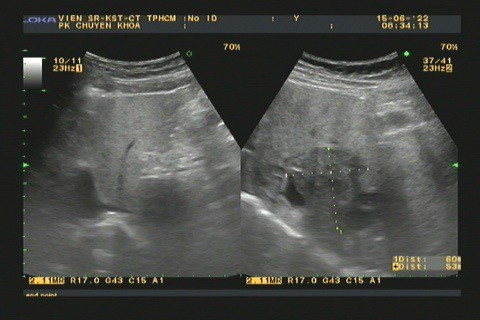

- Chẩn đoán hình ảnh: siêu âm, chụp CT phát hiên những tổn thương và biến chứng gan mật.

Hình 2.Tổn thương gan ở bệnh nhân bị nhiễm sán lá gan nhỏ